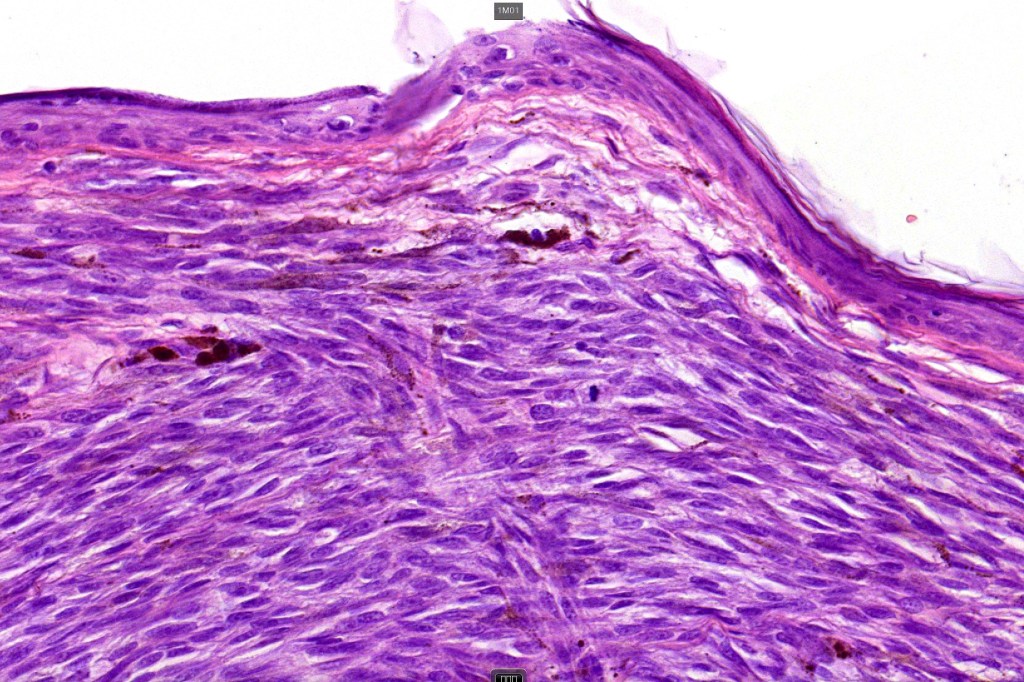

Histological features

•Develops within a precursor lesion as one or more nodules of epithelioid or spindled cell melanoma

•Nuclear pleomorphism with prominent nucleoli, mitotic activity & abnormal mitoses